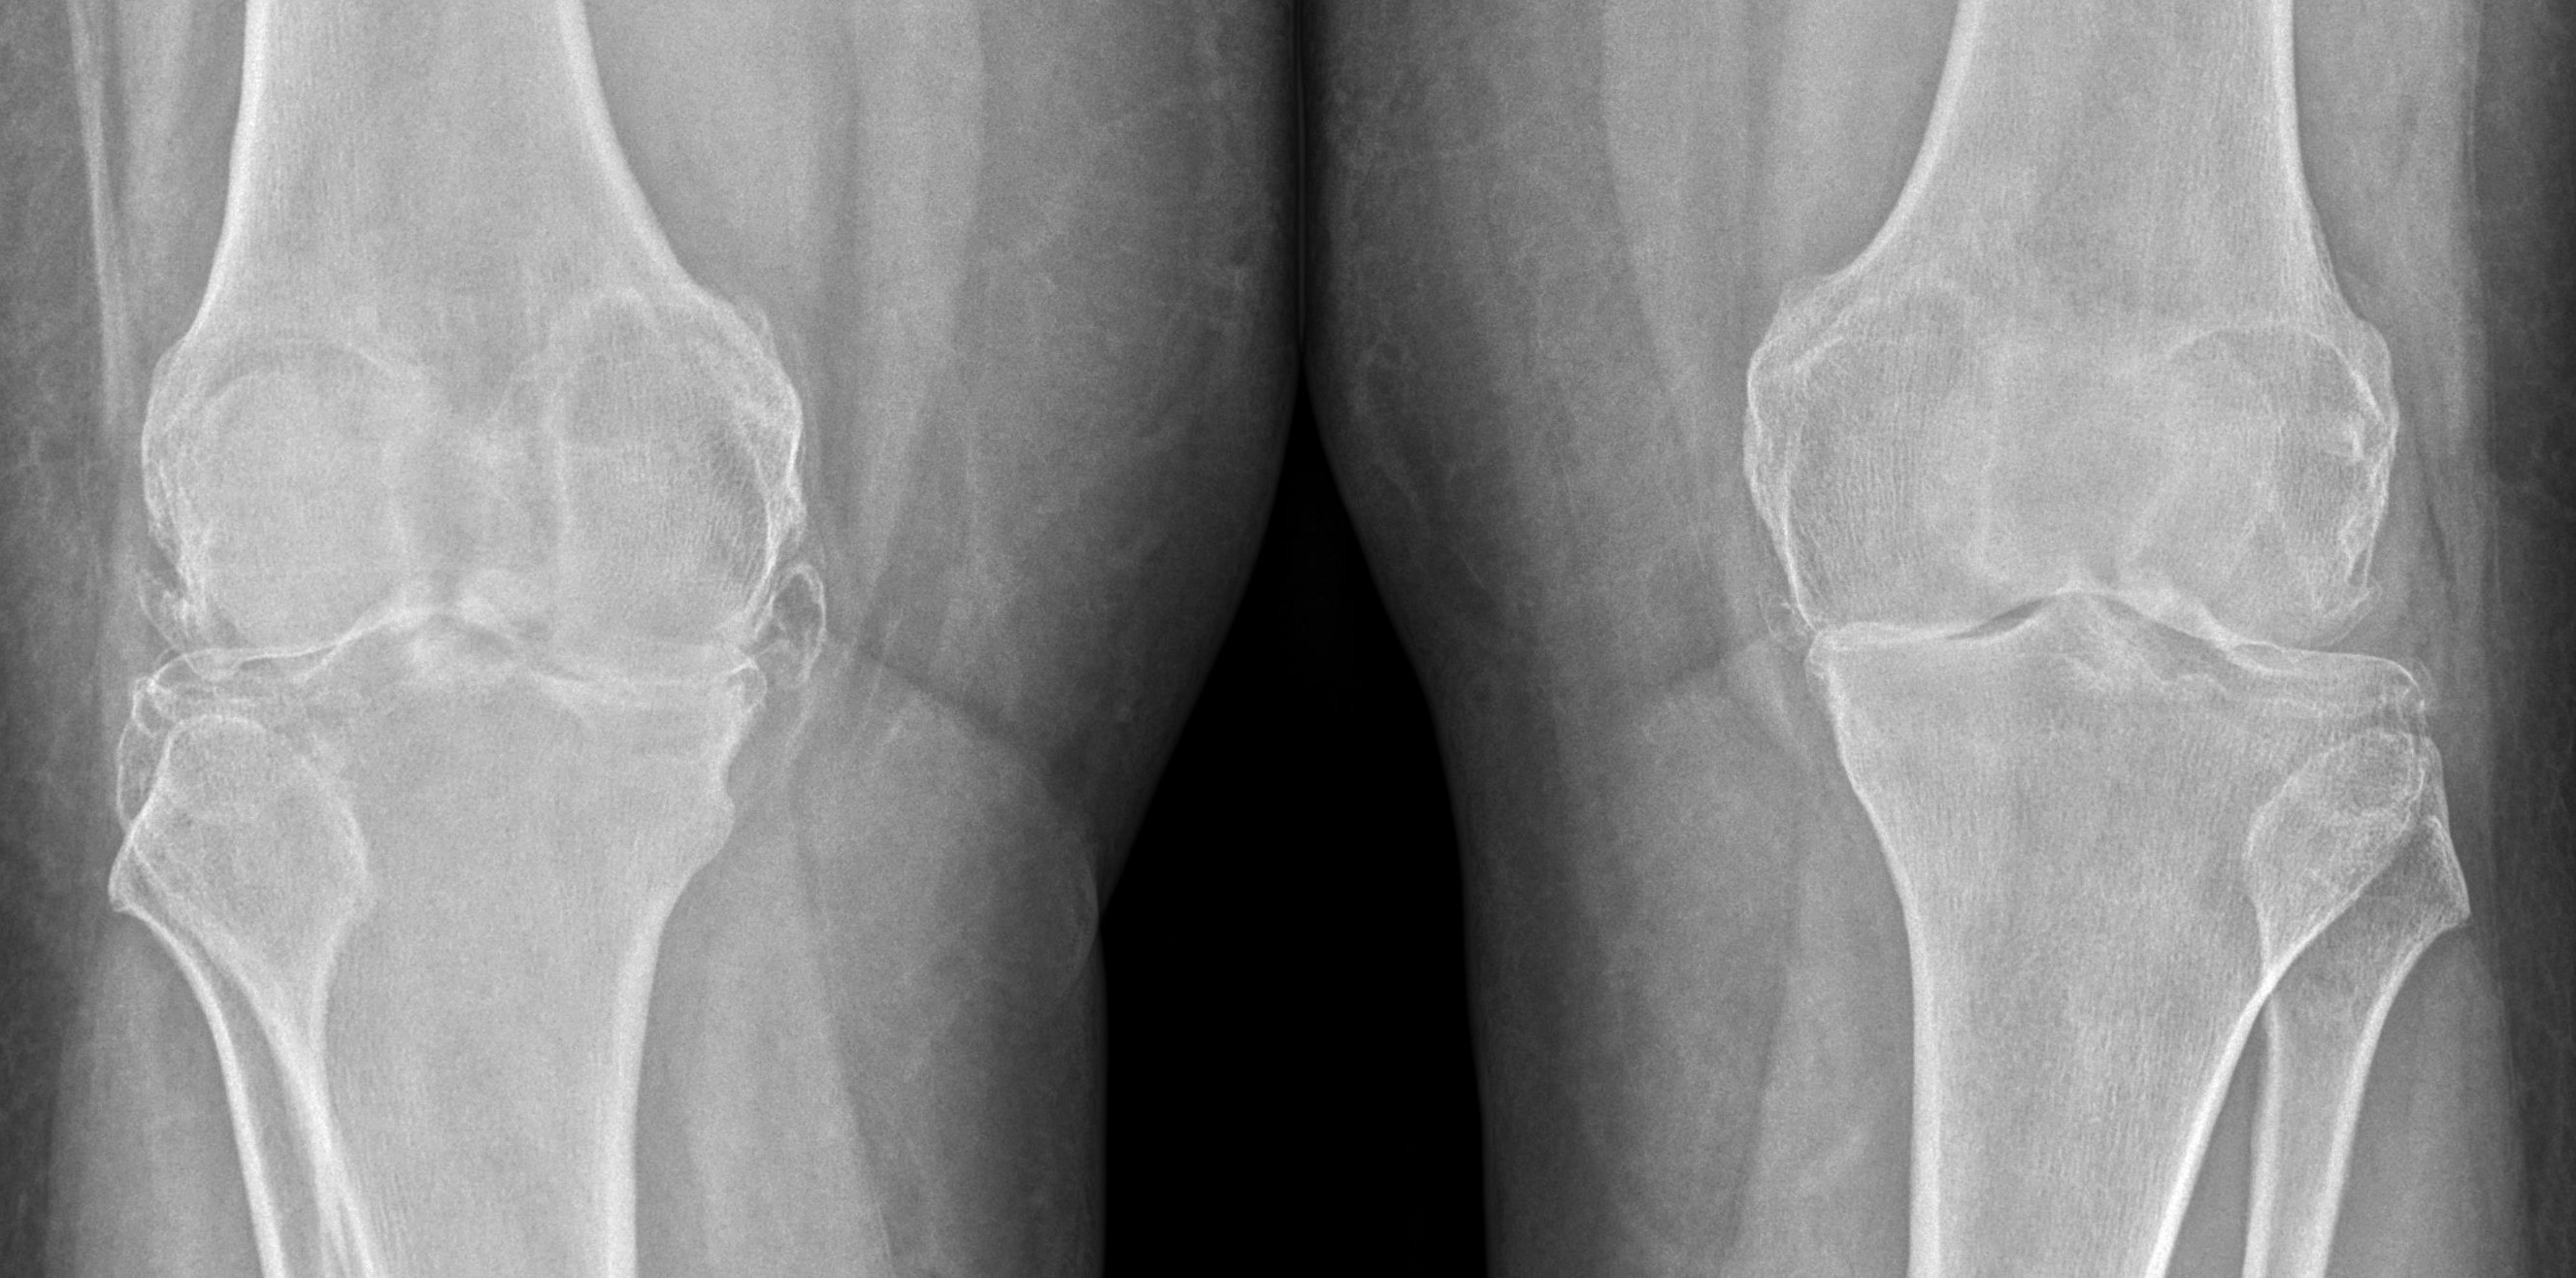

Немного вспомним. Остеоартроз — это дегенеративно-дистро-фическое заболевание суставов, характеризующееся первичной дегенерацией суставного хряща с последующими изменениями суставных поверхностей и развитием краевых остеофитов, что приводит к деформации суставов. «Остеоартрит» — синоним терминов «артроз» и «остеоартроз». А -ит на конце слова подчеркивает, что остеоартроз — это не только дегенерация сустава, но и воспаление, артрит (синовит), в суставе появляется патологическая жидкость («сары су»). Артроз коленного сустава (наиболее распространенный) называется гонартроз, тазобедренного — коксартроз. Если поражено много суставов, в том числе кисти — это полиостеоартроз («поли» — много). В народе эту болезнь называют отложение солей, хотя в суставе откладываются не просто соли, которые можно смыть, это твердые костные разрастания, остеофиты. Они бывают незначительные (в коленном суставе это 1-2 мм), средние — 4-5 мм и большие (свыше сантиметра). Остеофиты никуда не могут деться в результате терапевтического лечения, большие остеофиты чаще всего нужно оперировать. Об оперативном лечении — чуть позже.

Напомним основные клинические проявления остеоартрита: боль, деформация, крепитация («треск» при движении) и тугоподвижность сустава. Надо отметить, что просто хруст в суставах (без болей, припухания и «заклинивания») чаще всего нестрашен. А вот если хруст сопровождается болями или припухлостью — надо срочно искать причину. Для гонартроза, как и для других, очень характерна «стартовая боль» — боль в начале движения, ходьбе, при вставании. При коксартрозе типична боль при ходьбе, иррадиирущая (отдающая) в пах. Этот симптом (боль в паху при движении, в том числе при отведении ноги) может быть первым признаком очень грозного заболевания — асептического (аваскулярного) некроза головки бедра (АНГБ). Количество диагнозов «асептический некроз» чрезвычайно выросло в последнее время, в «эпоху COVID-19». Это связано как непосредственно с воздействием вируса, так и с бесконтрольным применением гормонов, в частности дексаметазона. Сегодня уже ясно, что дексаметазон никак не может помочь пациентам с COVID-19 при легком течении, он помогает только тяжелым пациентам и несколько уменьшает смертность больных, которые находятся на аппаратном дыхании и им требуется кислородная поддержка. Назначение гормонов пациентам с COVID-19 с легкой или средней степенью тяжести, наоборот, ведет к увеличению смертности. А частое применение дексаметазона может привести (и приводит!) к асептическому некрозу, что заканчивается неминуемой операцией.